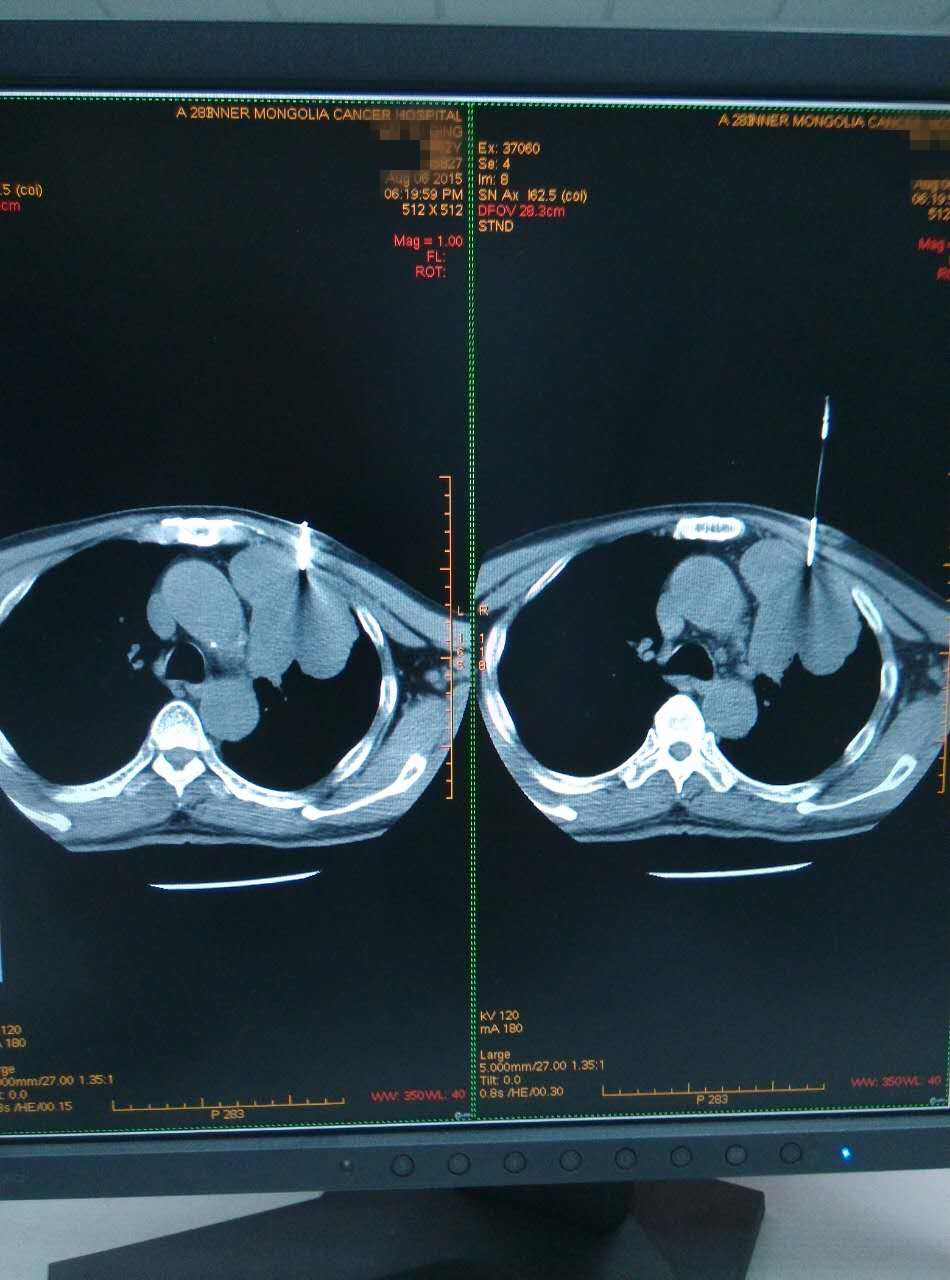

影像科自2015年7月开展CT引导下经皮穿刺活检术以来,一个月时间内,成功为9名患者明确了病理类型,为进一步个体化治疗提供有力支持。

CT引导下经皮穿刺活检术将影像诊断与病理诊断密切结合起来,成为沟通临床与病理诊断的桥梁,对促进肿瘤精准医疗发展具有巨大现实意义。该技术应用了圆柱切割型组织活检针,与以前使用的侧槽切割式活检针相比,该活检针可以多59%的组织标本,可以明显提高病理诊断的阳性率。

CT引导下经皮穿刺活检术具有快速、安全、创伤小、痛苦小、费用少、定位精确、检出率高、并发症少等优点,不仅解决了以往只能通过开胸手术或胸腔镜才能明确病理诊断的不足,而且明显减轻患者及家属的恐慌和焦虑心理,极大提高我院诊治水平。